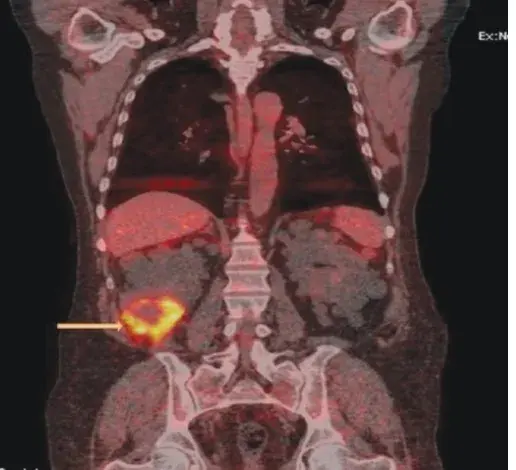

Os cálculos coraliformes são formados em sua maioria por cálculos de estruvita (fosfato amônio de magnésio) e possuem uma forte associação com infecção do trato urinário (ITU) causada por bactérias produtoras de urease. A formação desses cálculos é rápida, semanas a meses, e se não instituído tratamento adequado pode ocorrer invasão completa do sistema coletor